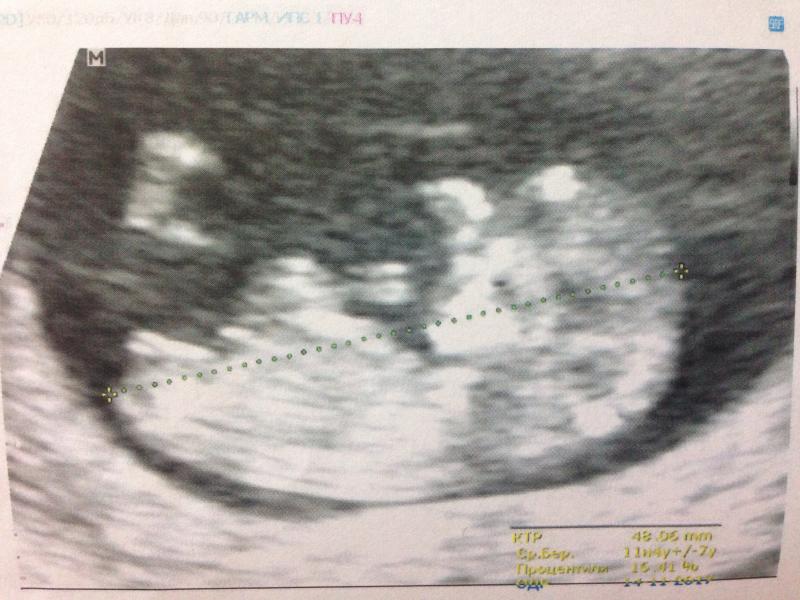

Сегодня была на первом скрининге! Так волновалась) Но стоило увидеть малыша и я сразу успокоилась ☺малыш махал ладошкой и пяточкой) я слушала сердцебиение и махала рукой в ответ☺

Все показатели в норме) можно расслабиться)